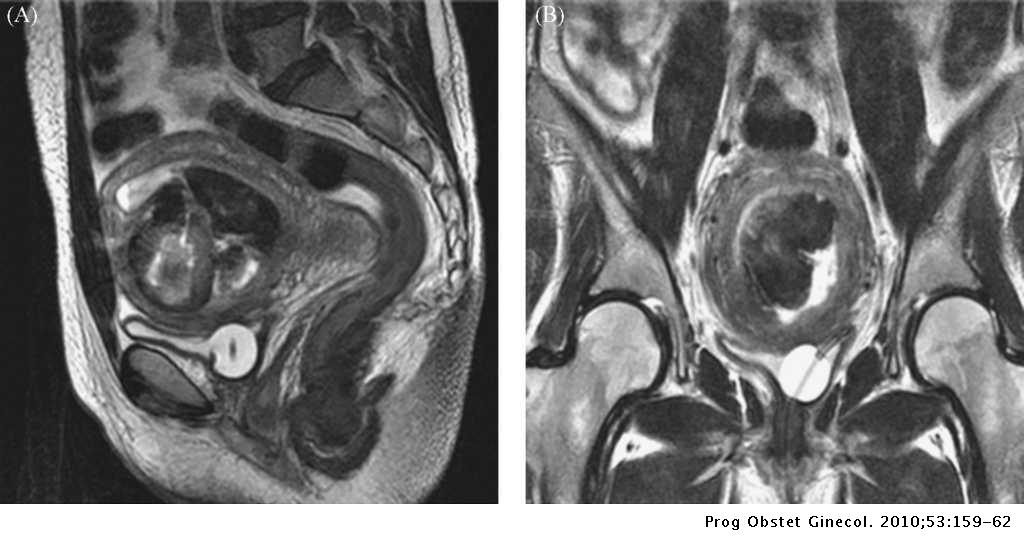

Mira Piomioma tras aborto de segundo trimestre de gestación | Progresos de tendencias